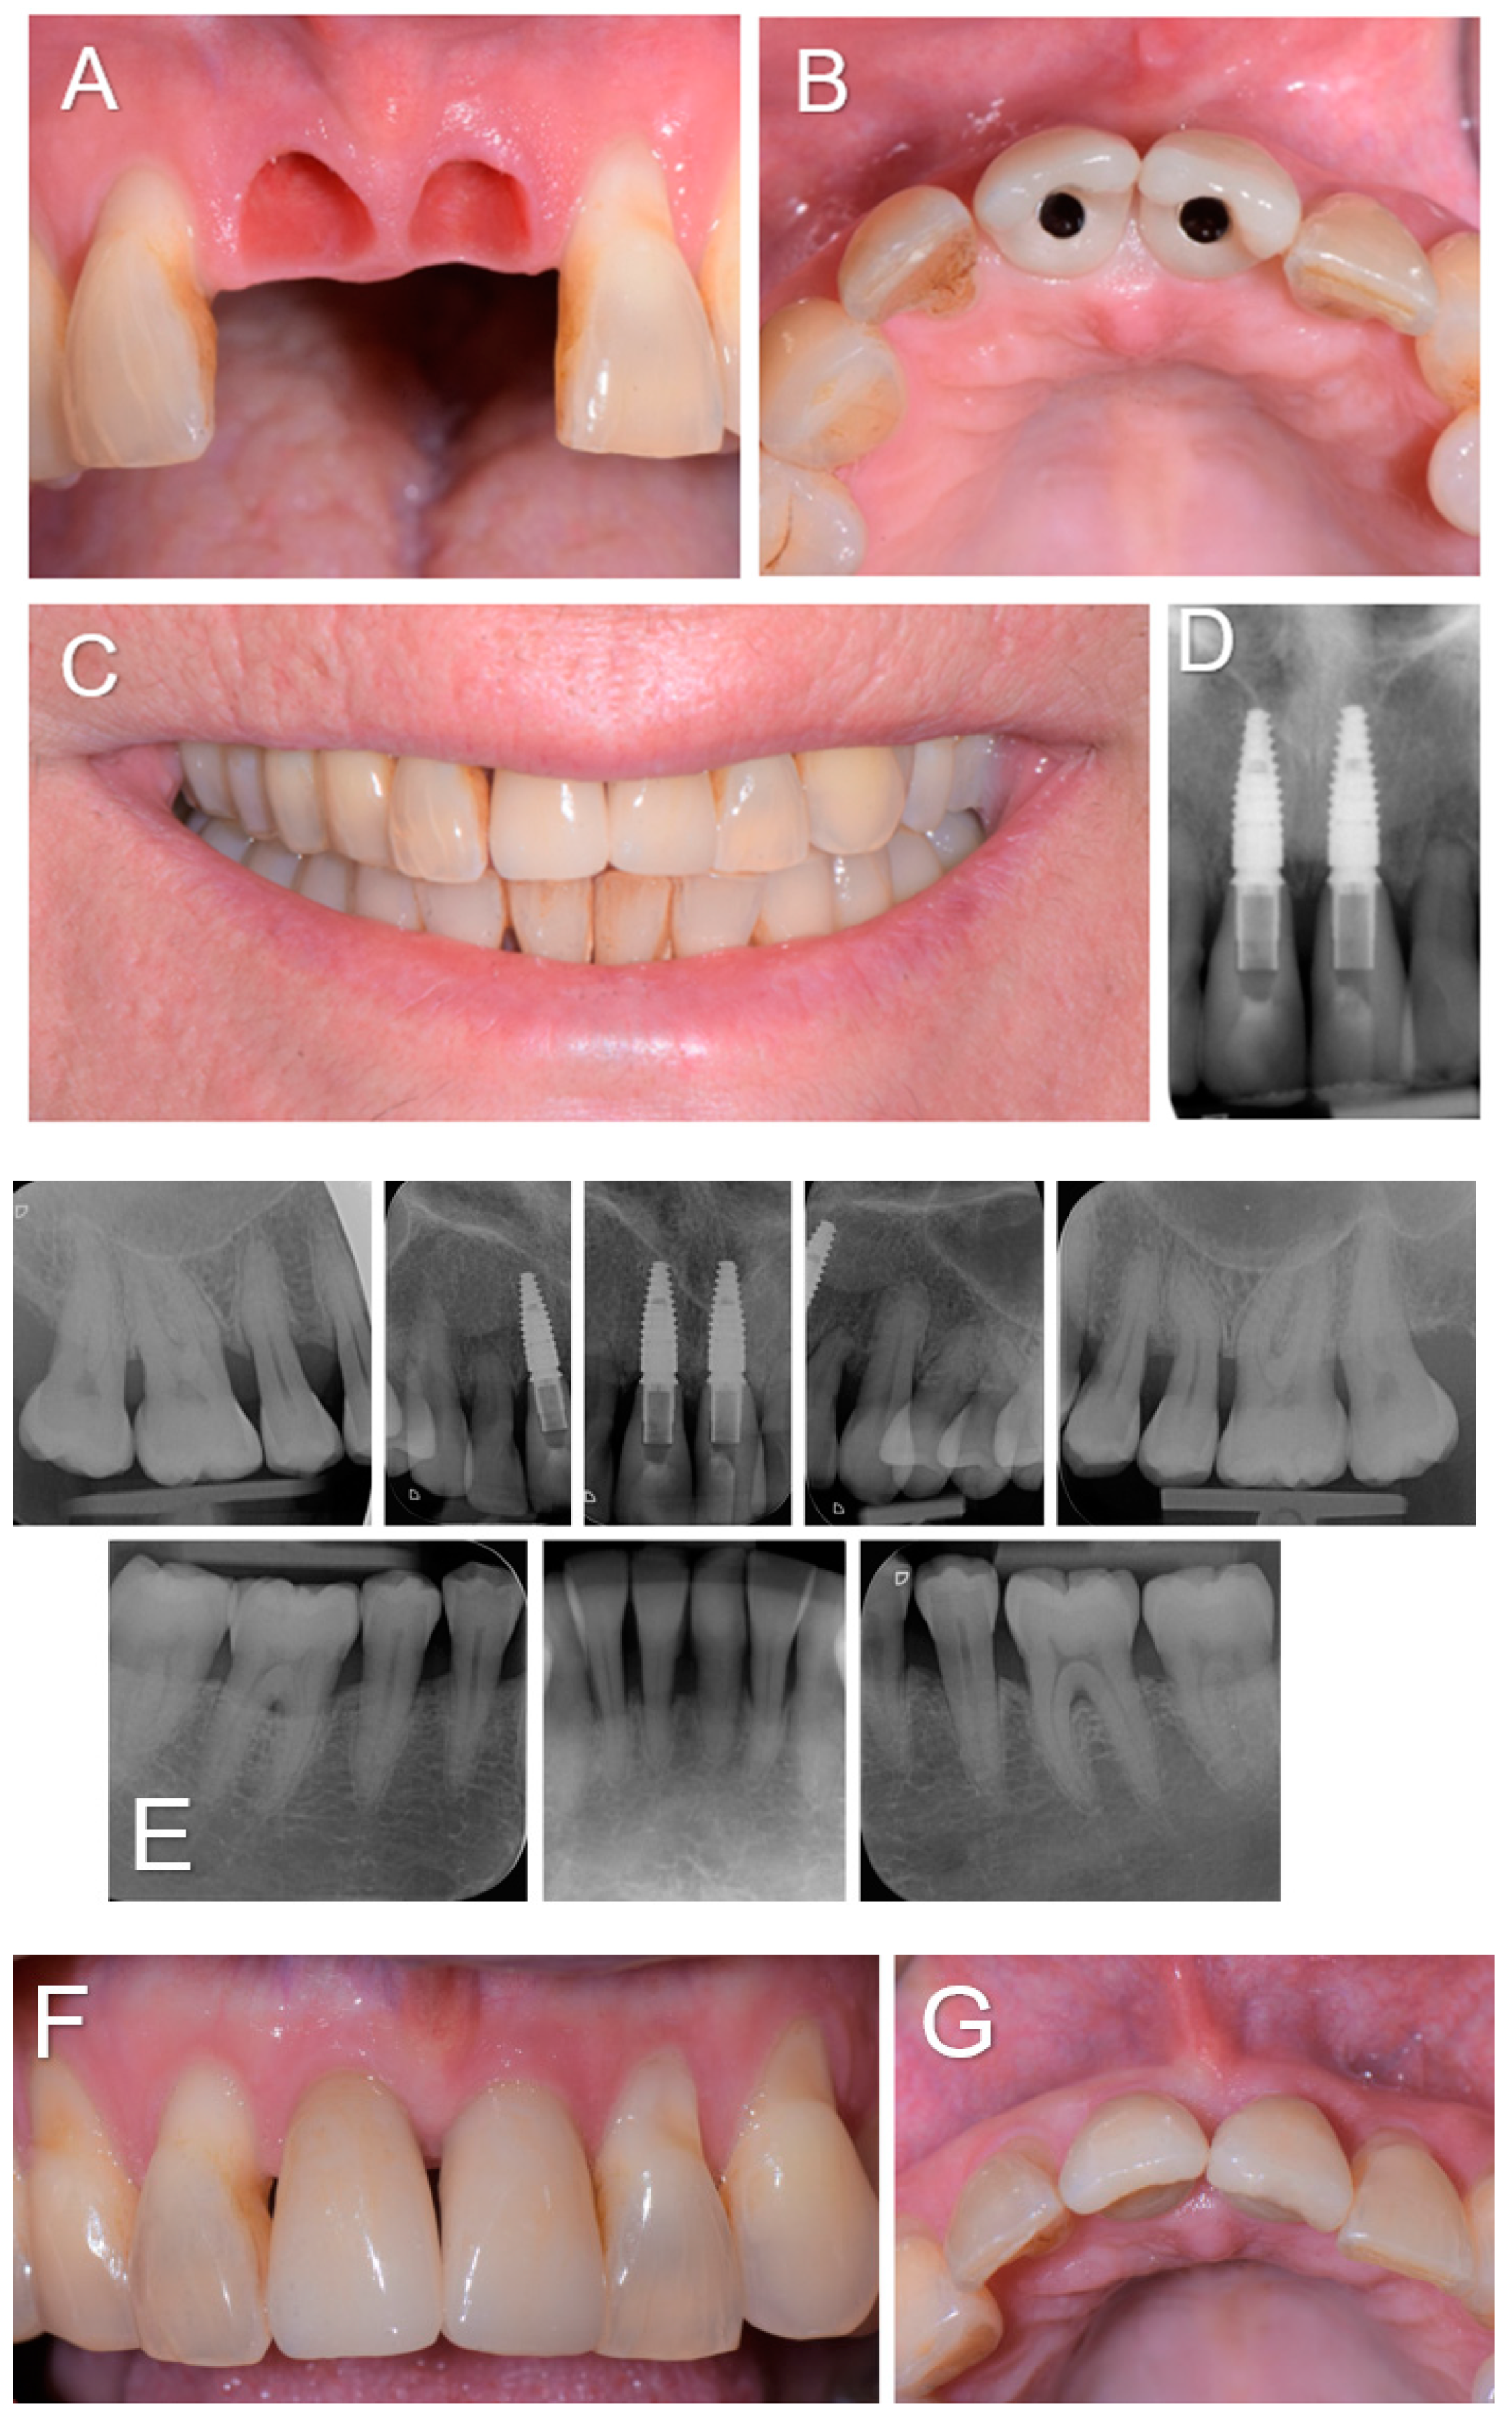

Our treatment consisted, for the first time to our knowledge, upon the patient’s awakening from general anesthesia and with her consent, of the replacement of the avulsed teeth by immediately inserting dental implants followed by immediate screw-retained coronal restorations (Figure 2). The immediate placement of dental implants in extraction sockets has proven to be a safe and viable treatment option in the case of socket type I [7]. This procedure became a strategy favored by clinicians owing to the associated advantages, such as reducing the number of surgical procedures, stress on the patient and morbidities, shortening treatment duration, and a better management of soft tissue and alveolar morphology. In our case, the socket was not ideal because it had suffered bone loss as part of the history of periodontal disease. Several studies have also reported that the high success rates of this technique were associated with the achievement of primary stability [8]. Bone anchorage for primary stability in immediate implantation primarily depends on the bone at the apical and palatal levels of the alveolus [8]. For this reason, particular attention must be paid to the proximity of neighboring anatomical structures such as the maxillary sinuses, nasal cavities, mandibular canal, and mental foramina. In the case of post-extraction sockets in the context of a reduced periodontium, achieving primary stability can be even more complex due to the reduced amount of bone and requires a more meticulous and precise surgical procedure. In our patient, one of the difficulties was to obtain primary stability because the residual bone height between the apical level of the sockets and the nasal cavity was 6 mm, which greatly limited the possibility of apical anchorage. Typically, bone augmentation simultaneous with immediate implantation is required to fill the gaps between the vestibular cortex and the exposed implant surface [8]. In our case, after placing the implants, the filling was carried out. However, the socket being of reduced height, the part of the dehiscent implant surface was limited to only 3 mm. Immediate implantation also offers the possibility of an immediate fixed provisional restoration, provided that primary stability is achieved and a sufficient insertion torque of around 35 N/cm is applied [9]. In our patient, although the periodontium was reduced in the context of a history of generalized chronic periodontitis, an insertion torque of 38 and 40 N/cm was obtained at the level of implants 11 and 21, respectively, and immediate restorations were carried out for the first time in this context. The patient followed regular dental and dental prosthesis checkups as well as oral hygiene recall appointments three times a year. During these appointments, the examiner recorded the clinical periodontal parameters and checked the status of the prosthesis. At the end of the appointments, a session of prophylaxis was performed, as necessary. At 3-year follow-up, she showed functional results without any recurrence or complications observed and the patient was fully satisfied with the treatment received (Figure 3). Our case highlights that immediate implant placement with immediate restoration can be a good valid alternative to standard treatment in case of a non-ideal socket with a history of periodontitis.

Figure 2.

(A–N). Intraoperative view showing sockets after curettage (A,B) and the control of the drilling axes of sites 11 and 21 (C,D), and an occlusal view showing implant bed preparation (E). The occlusal (F,G) and buccal (H) view after the placement of implants (Bone Level, Ø3.4 × 10 mm, Straumann, Switzerland) at sites 11 and 21, showing small buccal bone defect ‘’dehiscence-like’’ at sites 11 and 21. The buccal view with transfer device screwed onto the implants for impression taking (I). The clinical view showing the augmented sites using autogenous bone chips and alloplastic bone (BoneCeramic™, Straumann, Switzerland), after the impression (J) and 3 h later (K) during the fixation of the screw-retained temporary crowns (L,M) and the periapical 2D radiographs taken immediately after implant placement (N).

Figure 3.

(A–D). Soft tissue condition when the two screw-retained single-unit crowns (E-max. press) were delivered 3 months post-operatively (A,B), and the clinical and radiographic examinations at the 3-year follow-up (C–G).